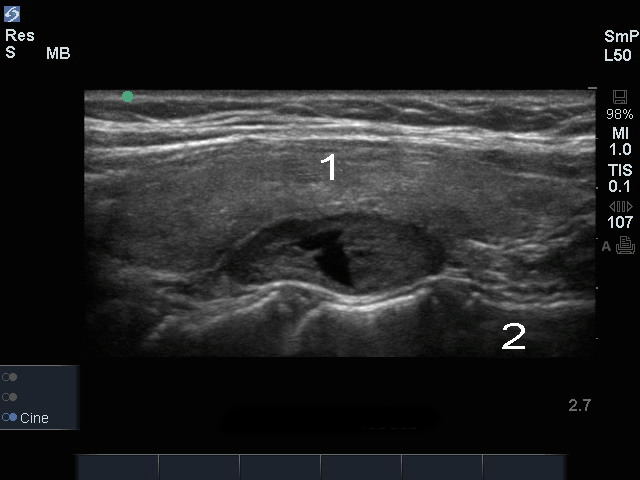

甲状腺甲状旁腺结节图像

甲状腺

颈椎